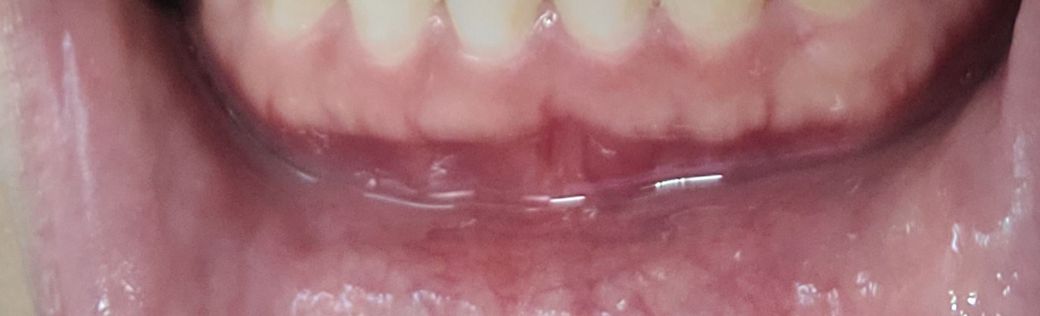

질문1.치아사진보면 잇몸이 볼록 나와있고 잇몸색도 흰색 분홍색 빨간색 섞여있는데 뼈 때문에 볼록한 모양이고 흰색이 섞여있는 건가요?

사진으로 보이는 잇몸은 부착치은이라는 조직으로 잇몸뼈에 단단하게 부착되어 있습니다.

따라서 부착되어 있는 잇몸뼈의 형태가 더 잘 보이게 되는데 치조골이 밖으로 자가 나오거나 한다면 그부위가 상대적으로 흰색으로 보일수 있어요.